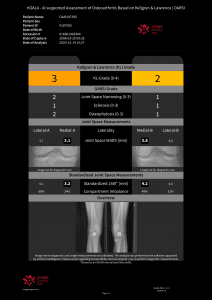

Dr. Richard Ljuhar:IB Lab is aiming to disrupt the way bone and joint diseases are currently being diagnosed. Technologies such as AI-supported software offer a novel way to translate imaging data into structured health information. IB Lab has developed (and certified) a unique MSK-analysis-focused digital workflow platform named IBLAB ZOO. Our deeptech technology is based on state-of-the-art image recognition algorithms and AI, trained on data sets extracted from an accessible image pool of 10 million medical images of various formats. The initial focus of our MSK platform has been on 2D X-ray modules for the knee, hip, hand and spine. The structured information extracted from imaging data enables us not only to disrupt the current workflow by providing standardization and increasing diagnostic accuracy, but also to create new insights into the prediction of disease onset and treatment outcomes.

Dr. Richard Ljuhar: Targeted treatment options ensure shorter periods of suffering, quicker recovery by applying objective assessment/progression measurements and prevention/delay of disease progression, leading to better outcomes. Enhanced and well-structured reports ensure ideal patient communication. MSK diagnoses are often time-consuming and subjective. IB Lab supports radiologists and orthopedists in their daily decision-making with standardized, fast and resource-effective AI-based software solutions for automated measurements on radiographs that accelerate the workflow and improve the time and quality of patient care.